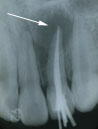

1.初診時

右から2本目の歯の根の先のあたりを中心に黒い影が見えます。

この歯の神経が死んでいるためです。

原因は以前の打撲。 |